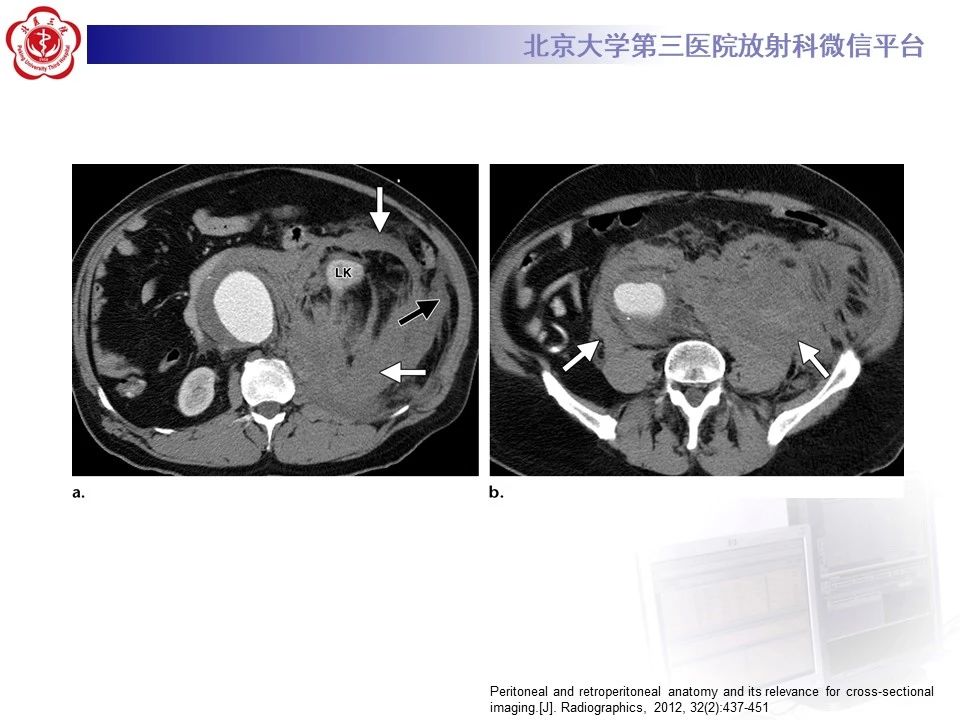

腹膜及腹膜后间隙的解剖,内附影像图谱